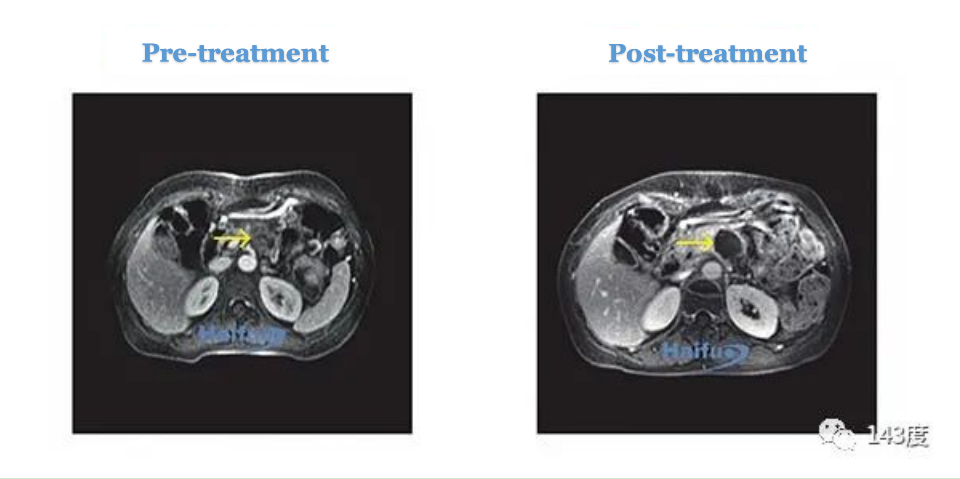

Pancreatic Cancer Treatment Case 1:

Patient: Female, 46 years old, tumor in the tail of the pancreas

The diameter of the tumor measures 34mm (anteroposterior), 39mm (transverse), and 25mm (craniocaudal). Following ultrasound-guided thermal ablation therapy, a follow-up MRI revealed that the majority of the tumor had been inactivated.

Pancreatic Cancer Treatment Case 2:

Patient: Female, 56 years old, pancreatic cancer with multiple liver metastases

Simultaneous treatment for both pancreatic and liver metastases using ultrasound-guided thermal ablation therapy. A follow-up MRI showed tumor inactivation, with clear and precise margins.